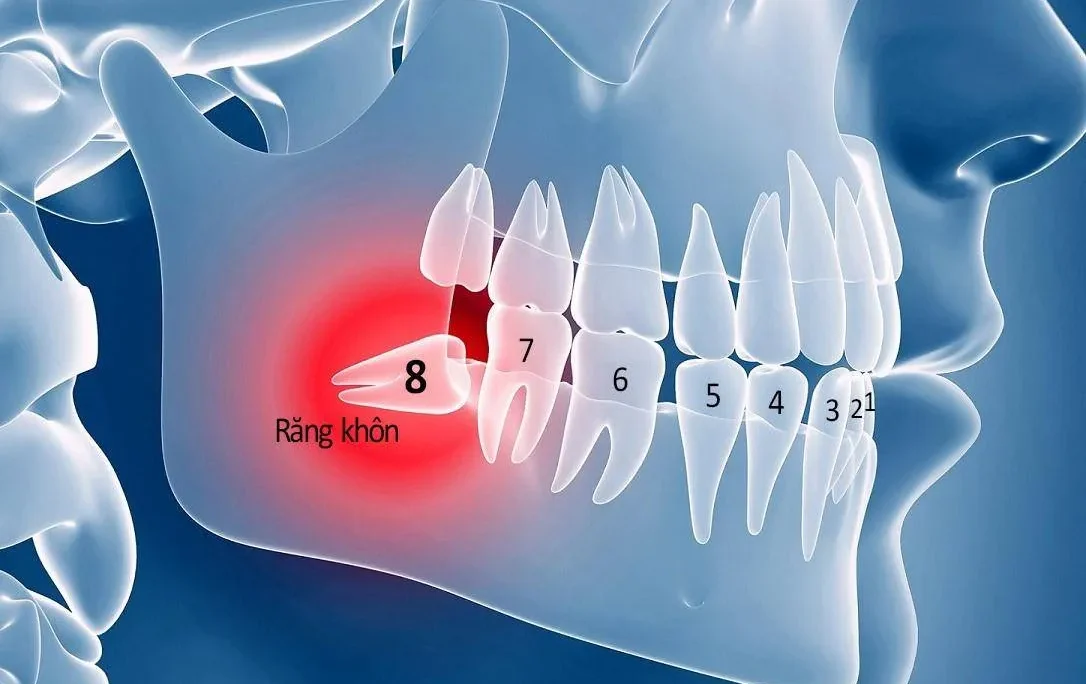

Trước khi biết răng số 7 bị sâu có nên nhổ không thì cần biết rõ về chiếc răng này. Ở người trưởng thành, bộ răng vĩnh viễn thường bao gồm 28 chiếc. Sau khi mọc đủ 4 chiếc răng khôn, tổng số răng sẽ là 32 chiếc. Trong đó, chúng ta có 4 răng số 7 đối xứng giữa hai hàm trên và dưới. Điểm đặc biệt của răng số 7 là cấu trúc chân răng khác nhau giữa hai hàm. Răng số 7 ở hàm dưới thường chỉ có 2 chân. Trong khi răng số 7 ở hàm trên có tới 3 chân. Từ đó giúp tăng khả năng chịu lực nhai.

Đây là chiếc răng có kích thước lớn. Nó đảm nhận chức năng quan trọng trong việc nhai và nghiền thức ăn. Răng số 7 cùng với răng số 6 chịu trách nhiệm chính trong việc nghiền nát thức ăn. Quá trình nhai của hai chiếc răng này không chỉ làm nhỏ thức ăn. Nó còn hỗ trợ trộn thức ăn với enzyme trong nước bọt. Từ đó giúp quá trình tiêu hóa ở dạ dày diễn ra hiệu quả hơn. Theo các chuyên gia, khả năng nhai của răng số 7 được đánh giá cao nhất trong hệ thống răng. Nổi bật hệ số 5, vượt trội hơn các răng khác.

Vì tầm quan trọng đó, bất kỳ vấn đề nào xảy ra với răng số 7 đều ảnh hưởng lớn đến khả năng nha. Tổn thương răng số 7 không chỉ gây khó khăn trong việc ăn uống. Nó còn có thể ảnh hưởng đến răng số 7 đối diện hoặc răng số 7 ở hàm còn lại. Từ đó làm suy giảm toàn bộ chức năng nhai và sức khỏe răng miệng.

Vừa rồi chúng ta đã biết rằng răng số 7 bị sâu có nên nhổ không. Việc nhổ răng số 7 là quyết định quan trọng. Nó chỉ được thực hiện khi răng không thể bảo tồn hoặc trong những tình huống bắt buộc. Các trường hợp phổ biến cần nhổ răng số 7 bao gồm:

- Viêm buồng tủy: Tình trạng viêm lan rộng không thể kiểm soát bằng các biện pháp điều trị thông thường.

- Viêm chóp răng hoặc viêm nha chu nghiêm trọng: Vi khuẩn đã xâm nhập sâu vào trong. Gây tổn thương lớn, không thể khắc phục. Thậm chí nguy cơ làm trầm trọng thêm tình trạng viêm nhiễm.

- Chấn thương nghiêm trọng: Răng số 7 bị tổn thương do tai nạn, va đập. Từ đó dẫn đến tình trạng mẻ, sứt, vỡ, hoặc gãy. Đồng thời không thể phục hồi bằng trám, bọc sứ, hoặc điều trị tủy.

- Sâu răng nặng dẫn đến chết tủy: Răng số 7 bị sâu nghiêm trọng. Lúc này cấu trúc răng bị phá hủy hoàn toàn, tủy răng chết. Các biện pháp nha khoa không còn khả năng cứu chữa

- Phục vụ chỉnh nha: Trong một số trường hợp chỉnh nha hoặc niềng răng, bác sĩ có thể yêu cầu nhổ răng số 7. Từ đó tạo không gian cho việc di chuyển răng và đảm bảo hiệu quả chỉnh nha tối ưu.